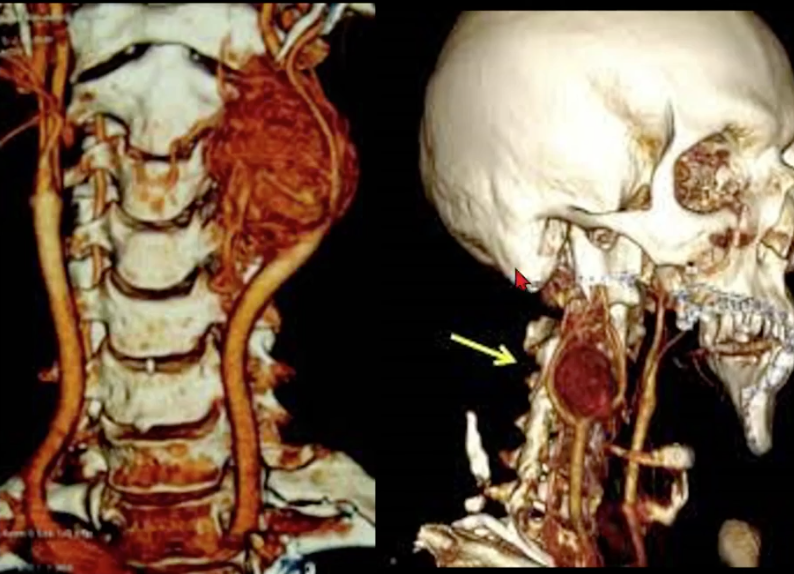

Roubo da subclávia

Obstrução proximal da subclávia com inversão de fluxo da vertebral e da mamária para irrigar o braço;